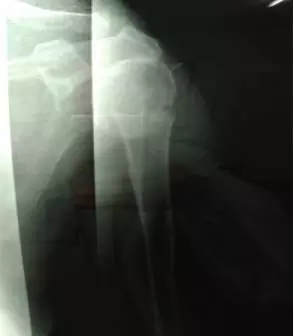

整復(fù)后復(fù)查X線片,骨折端位置良好。

鮑阿婆及家人看過(guò)片子后也十分滿意,“都說(shuō)廣安醫(yī)院醫(yī)生的技術(shù)真是好,早知道3年前右手骨折在你們這里看,就不用吃那么多苦了”。鮑阿婆表示。

整復(fù)后